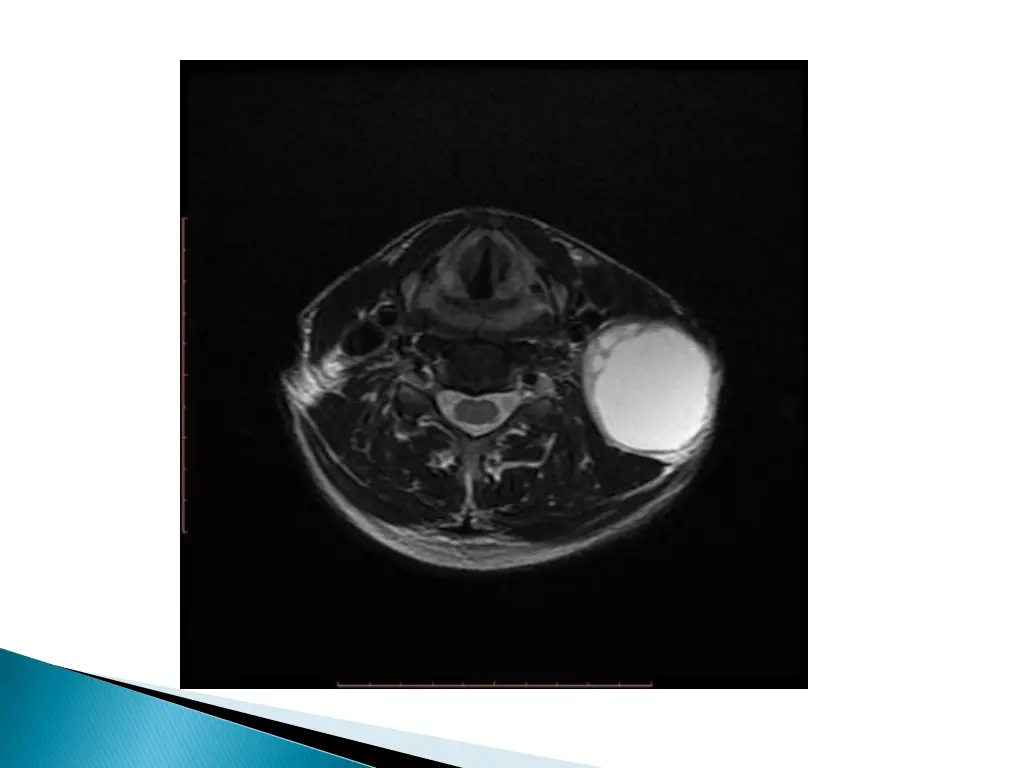

UNCOMPLICATED CYST : hypo on T1W and hyper on T2WI with smooth non enhancing wall. INFECTED/HAEMORRHAGIC CYST: thick irregular wall with enhancement. variable signal intensities depending on the protein content.